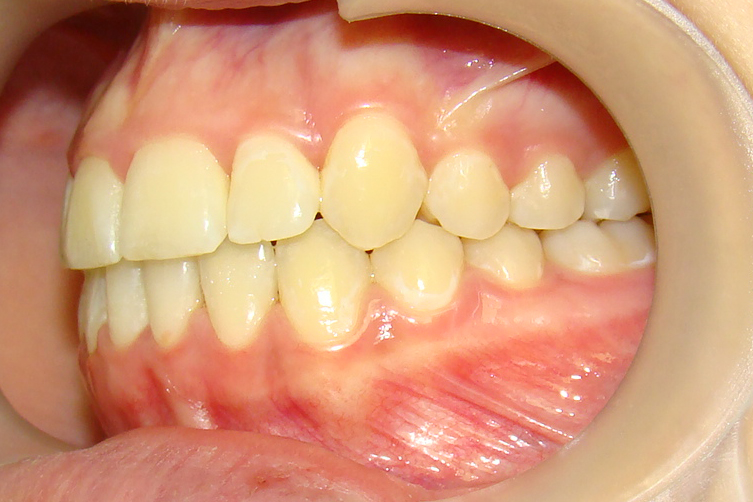

А это уже молодой человек 10 лет. Тоже получилось справиться без удаления. Хоть оно и было показано. Но мальчик очень упорно носил специальные аппаратики и резиночки. Покажу со всех сторон. Этот случай победил в конкурсе на конференции